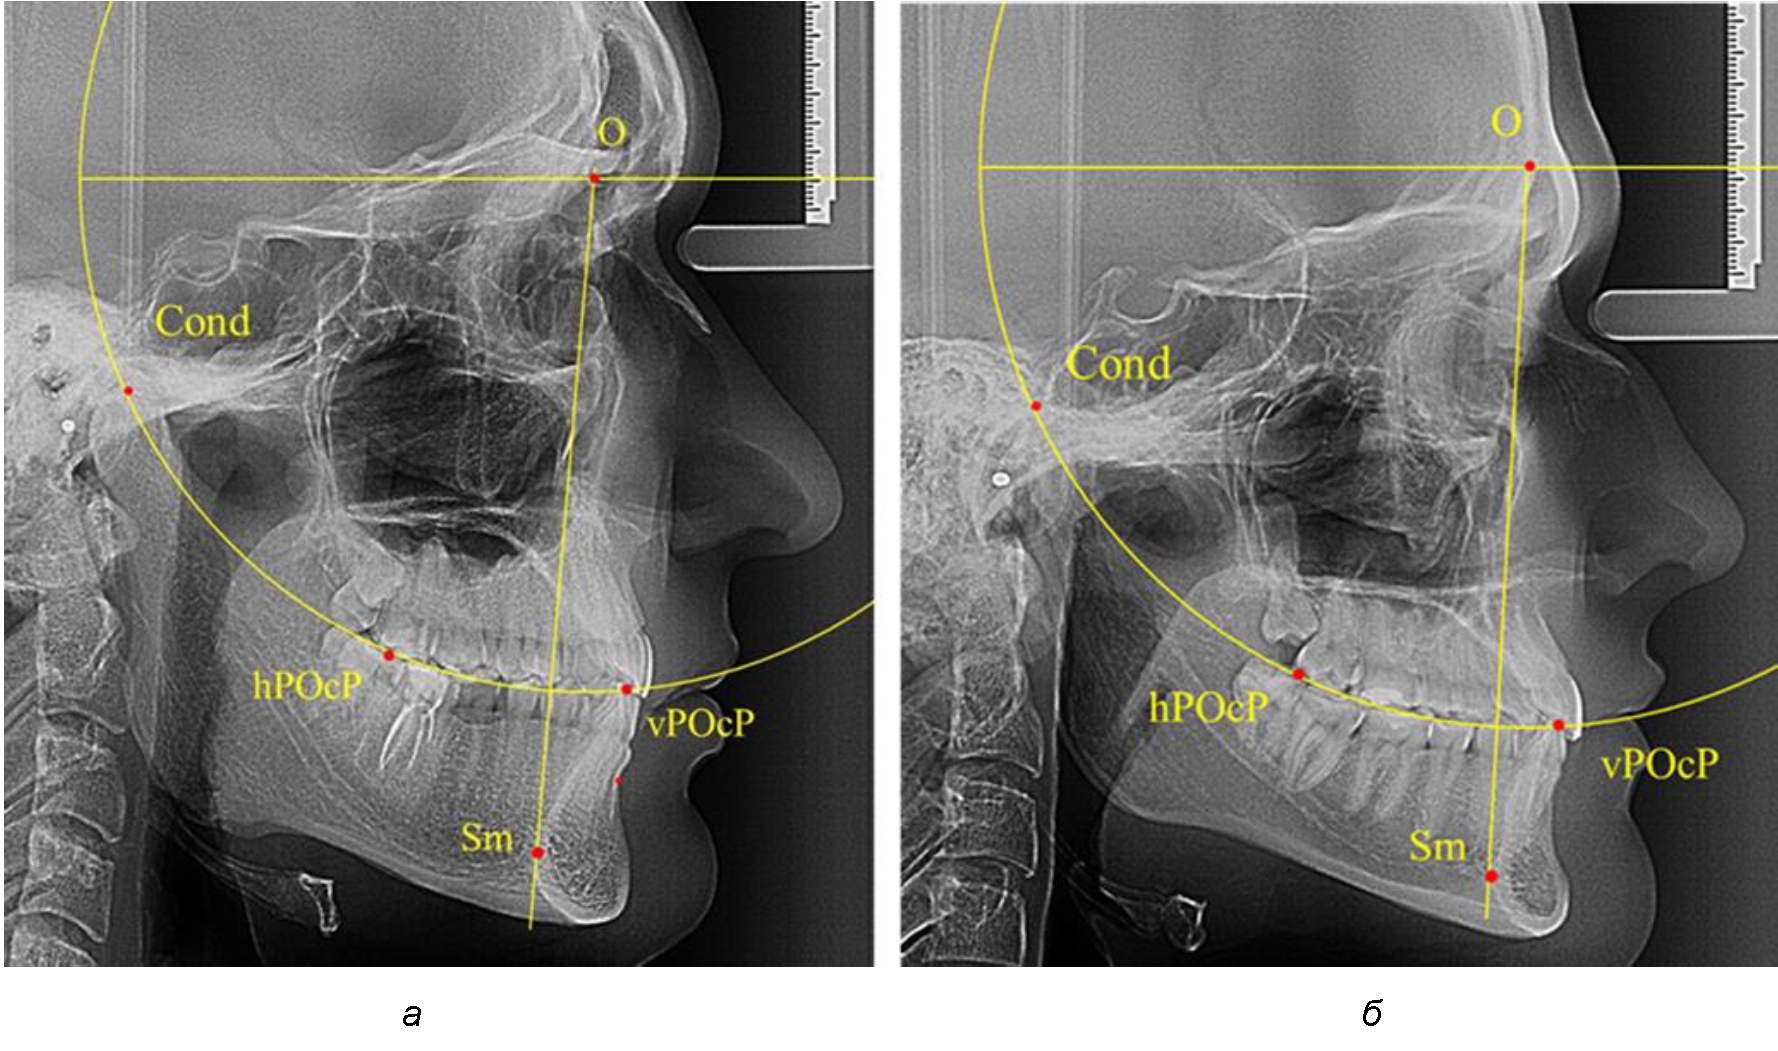

Результаты исследования рентгенограмм с мезотрузионным типом резцов показали, что линия Bimler проходила позади первых премоляров у людей с широким типом подбородочного выступа, однако окклюзия была физиологической и не требовала удаления премоляров, что носило рекомендательный характер при проведении подобных исследований при аномалиях прикуса. У людей со средними формами подбородочного выступа линия Bimler проходила впереди первых премоляров (рис. 2).

Аналогичная ситуация была у людей и с узкими вариантами подбородочного выступа.

Таким образом, при мезотрузионном типе зубочелюстных дуг расположение премоляра впереди линии Bimler при широких вариантах подбородка не может быть критерием выбора экстракционных методов лечения.

Рис. 2. Положение первых верхних премоляров при мезотрузии с широкими (а) и средними (б) размерами подбородка